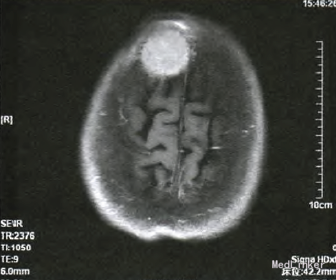

人院行体格检查发现:右侧前额部包块,隆起明显,直径约5cm,形态规则,表面光滑,质软,边界清,无触痛,活动度差,周围可触及动脉搏 动。患者未诉有任何疼痛、瘙痒等不适,追问病史,诉3个月前偶然发现该肿物,生长缓慢。右侧前额部包块超声检查结果见:皮下软组织内可探及范围约2.8cm×2.2cm×3.2cm的低回声包块,侵犯颅骨,形态尚规则,边界尚清,内回声尚均匀,可及动静脉血流信号,可引出动脉频谱,Iu:0.90。考 虑恶性肿瘤转移可能。行头颅MRI增强扫描,提示:右额骨区可见35mmx35ram×37ram大小占位病变,病变破坏颅骨内外板并膨胀性改变,增强扫描 明显强化;余颅内未见明确异常信号,脑室系统及脑沟、脑裂增宽;中线结构无移位,符合恶性肿瘤改变。

据患者病史、查体及辅助检查考虑诊断:①右额骨肿瘤;②甲状腺癌术后肺转移;③高血压病2级中危;④2型糖尿病。完善术前常规检查,行额部开颅右额骨肿瘤切除+硬膜修补术+钛板植入术,术中取部分肿瘤组织送冰冻病理检查示:(右额)纤维结缔组织及骨组织内可见癌浸润,形态符合甲状腺来源。术后肿瘤组织石蜡病理报告为:甲状腺癌颅骨转移,组织形态学符合甲状腺滤泡癌;颅骨四周切缘未见癌。术后行头至腹股沟PET/CT检查:“甲状腺癌术后、I内放疗术后、肺转移瘤粒子植入术后、右额骨转移瘤术后,右额部术后改变,右额部皮质局部葡萄糖代谢弥漫性增高,考虑反应性增生;双肺多发结节,符合转移改变,左下肺内基底段病灶仍有代谢活性;双肺多发陈旧性条索,纵隔及肺门炎性淋巴结;甲状腺术后缺如;左肾囊肿;腹盆部葡萄糖代谢 显像未见异常。